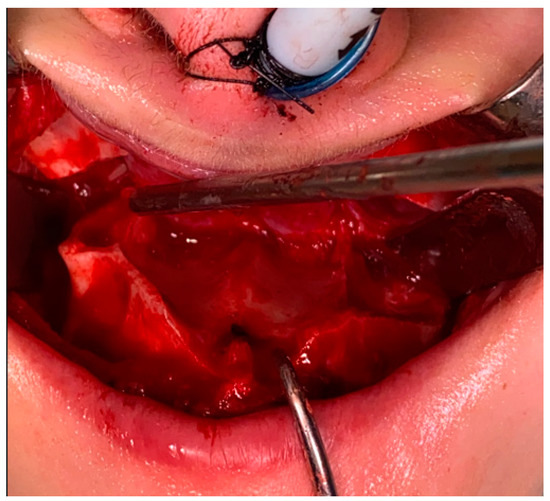

- (2)

- Type 2 in-pure SSS (iSSS) (Figure 3, Figure 4 and Figure 6) related to maxillary deformation (might be related to maxilla-mandibular skeletal class II/III deformities or others), clinically asymptomatic, not related to trauma or surgery, 1–3 MS walls retracted, OMC clear, no opacification, like suggested by Lee et al., the “not so silent sinus” [18];